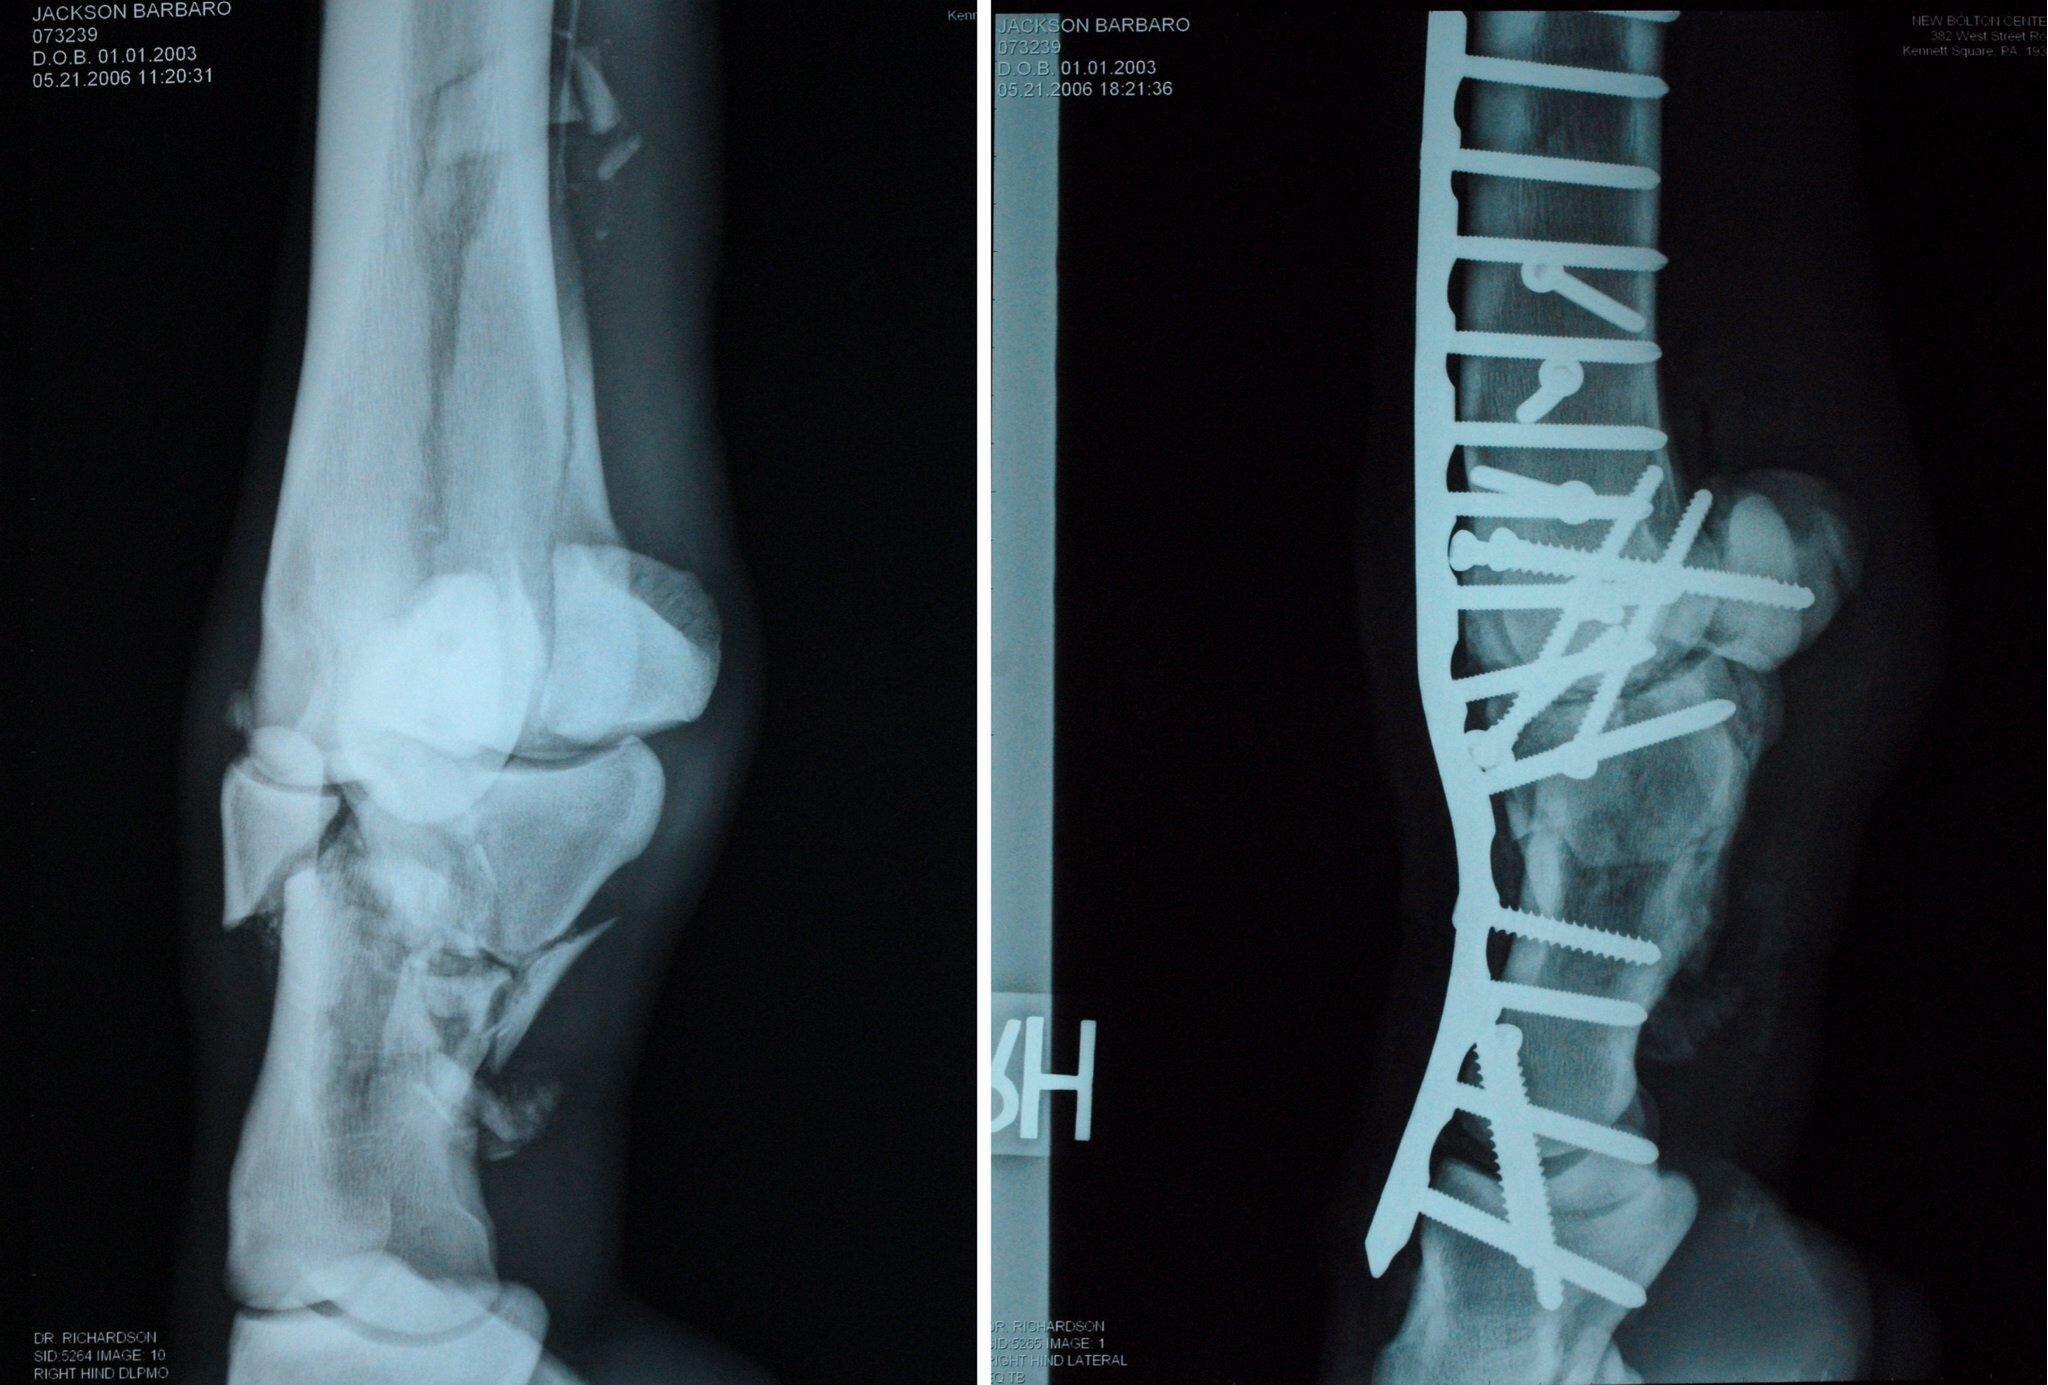

原因是,其參加海之森賽馬比賽時,不慎受傷,

造成了“無法修復的韌帶斷裂”,獸醫的建議是安樂死,這種人道行爲得到了馬主任的同意,爲了安撫民心官方回覆是,我們這麼做是爲了減少它的痛苦!網友卻給出了自己的理解,腿斷就沒用了,纔不養!

退一步講傷了腿養不好。沒有經濟效益,資本逐利有給馬看病做康復的錢,再培育新賽馬綽綽有餘!什麼叫外行口嗨,內行無語,這就是了,只能說網絡懂王只會敲鍵盤,不調查就亂下定論!輪愛馬誰有馬主人捨得下本,論專業有人難道比獸醫更懂,安樂死的決定並非輕易下!賽馬不止在賽場上獲得獎金,退役後的配種費更是大頭!這匹奧運賽馬真救治成功帶來的效益只會更多!美國淘氣鬼都17歲了,配種費照樣高的嚇人,一次180萬!

體型這麼大又不像貓狗之類的一樣跳着走,兩三噸的重量全壓在了三條腿上,野外肯定成爲食肉動物的自助餐,多虧了當地亞洲象救治醫院,給它裝上了假肢!三腿變四肢熟悉的感覺回來了,輪到同樣四條腿的馬,可沒那麼好運了,美國著名賽馬巴巴羅治了倆月的骨折,最後死於治了半年都治不好一直復發的蹄葉炎,

日本曾獲得彌生賞、皋月賞、菊花賞三次連勝的著名賽馬“櫻花星王”,遇了左前蹄韌帶斷裂,主人立馬決定手術,問題養傷期間左蹄沒好,右前蹄因負擔過重出現蹄葉炎,四肢夭折倆,“櫻花星王”體重暴跌,搶救四個月後走上了噴氣機的老路,安樂死,以上案例全在印證,治療是在延長痛苦,熬過一段時間最後疼死!名貴賽馬但凡能有治,誰願意安樂死呢,畢竟馬主還靠着他們賺錢,配種呢,

馬腿骨折治療後,身上的重量勢必讓其他三條腿承擔,久而久之,

銳利的蹄骨就會慢慢地戳破蹄壁,身要靜養的傷,馬可不理解,躺治它的病,

站要他的命,越疼越跺腳,非把導致痛苦的罪魁禍首給震出來,馬很容易應激,蠻力執行亂誰甩的斷腿掙扎能把四條腿踢斷仨,這種行爲在醫生看來,併發症一大堆更難好,陷入惡性循環,馬主天天付護理費,病情反而因動物的不配合加重了,農場主才狠心安樂死!如果是富豪的馬,通常用專業的裝置會把馬懸空,僱人日夜看護,